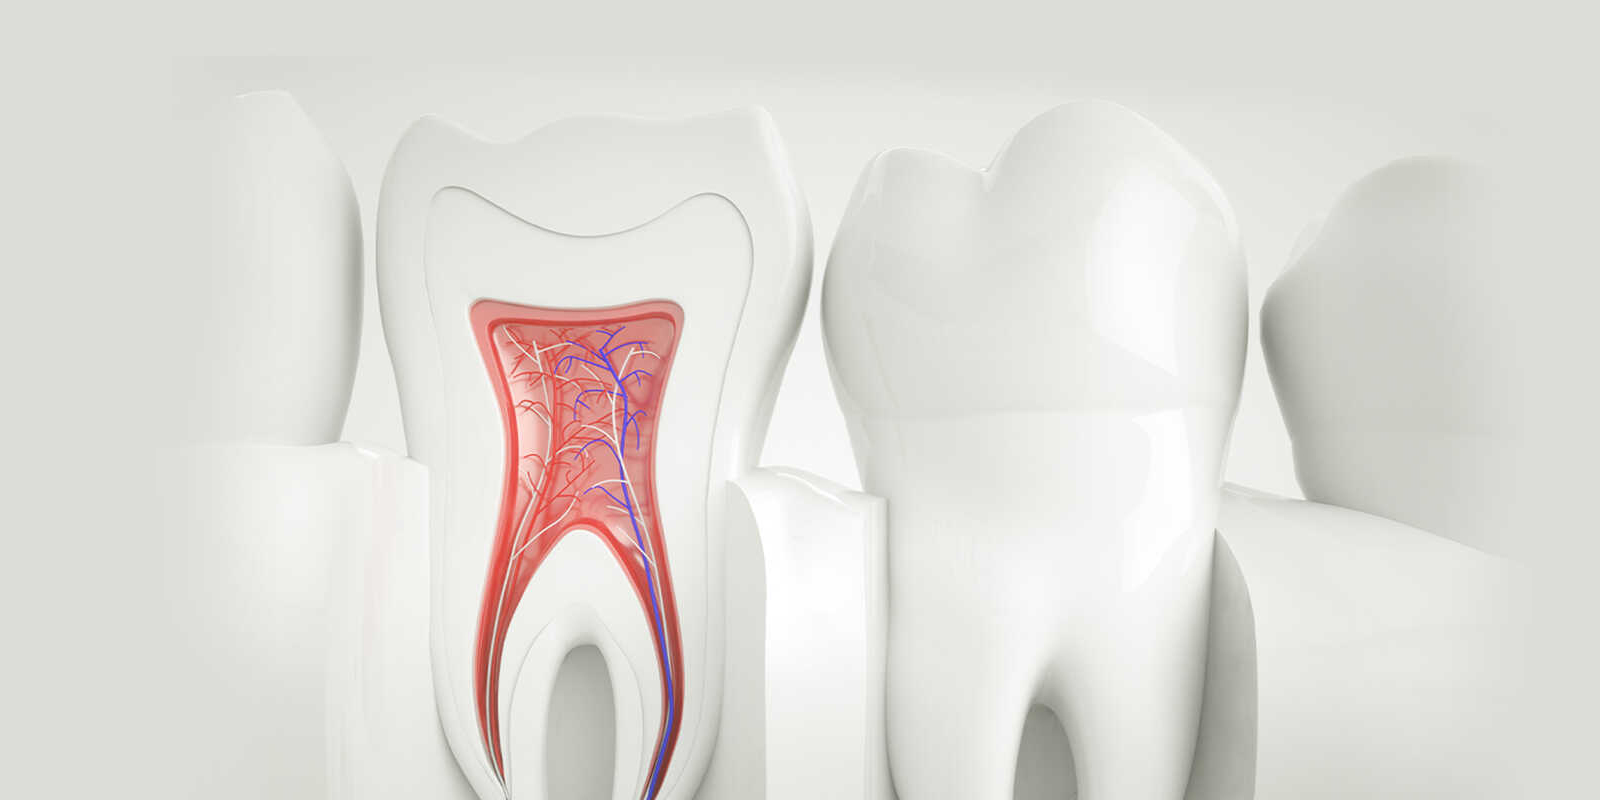

歯の根っこ(神経)の中から痛みや腫れの原因である「感染した汚染物」を、取り除く治療です。

針のような道具を使って、感染した汚染物をとりのぞいていきます。

汚れを取り除いた箇所をキレイに清掃・消毒して、お薬で埋めるまでが根管治療です。

歯の神経(歯髄)が残っている場合の治療方法は「抜髄」とよばれます。文字通り「歯の神経を抜く」治療です。